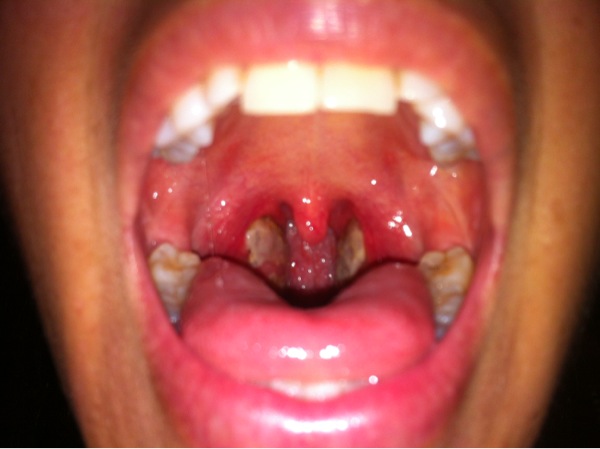

It means inflammation of tonsils. In tonsillitis, patient suffer from swelling of tonsils, irritation, pain & difficulty in swallowing.

Because of recurrent tonsillitis, there can be pus formation in tonsils which is very painful & difficult to treat by medicine (other pathies).